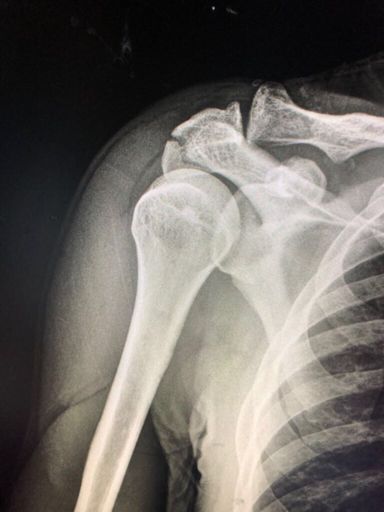

Mtb interrompido por mais uma queda. 30 dias de molho...